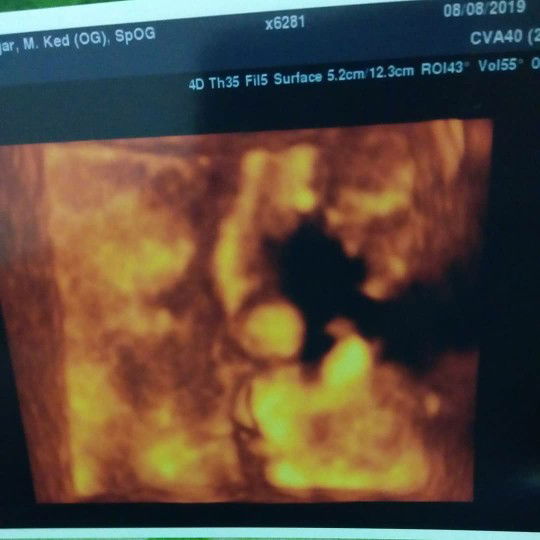

Hai.. Bun td aku kontrol k rs, kata dokter bayinya kelilit tali pusar 1 lilitan,untuk hasil yg lainnya Alhamdulillah bagus semua dan posisi kepala bayi udah masuk panggul,perkiraan lahir dari tgl 19 Agustus jd 23 Agustus, kalo belum ada tanda" mau ga mau harus d sesar Kta dokter nya, aku jd deg degan Bun ?